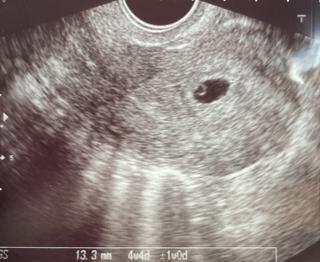

3回の人工授精と2回の体外受精を経て妊娠しました。前回は、化学流産で胎嚢確認できなかったので、胎嚢と卵黄嚢が見れて嬉しいです。大きさは13.3mmでした。

このまま、順調に成長してくれることを願って2週間後の心拍確認に臨みます!!